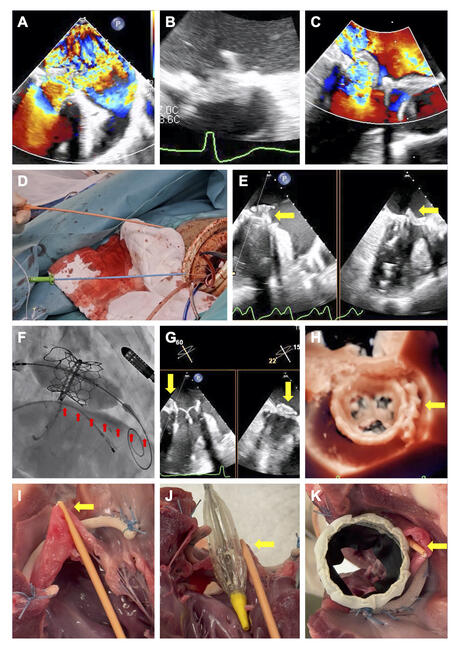

A 69-year-old man had previously undergone mitral valve repair in 2008 with a 30-mm Carpentier-Edwards Physio II annuloplasty ring (Edwards Lifesciences) and a GORE-TEX artificial chordae (Gore Medical) to the AMVL in 2008. Sixteen years after the procedure, he developed severe mitral regurgitation (MR) with ruptured artificial chordae, flail AMVL, and restrictive posterior mitral valve leaflet (Figure A). His left ventricular ejection fraction was preserved. He had a high risk of LVOT obstruction from a long AMVL (37.1 mm). The consensus of the heart team was to attempt repair using the NeoChord DS1000 device (NeoChord, Inc.); if results were unsatisfactory, it was decided to perform TMVR with the UNIFOLD technique.

During the operation, satisfactory MR reduction could not be achieved despite successful NeoChord insertion to the A2 (Figure B and C); elective conversion to TMVR was performed. The septum was traversed using VersaCross (Boston Scientific), and the mitral valve was crossed using an Agilis NxT steerable introducer (Abbott) and a pigtail catheter. A SAFARI2 extra small curve guidewire (Boston Scientific) was inserted to the apex, and transeptal access was dilated. UNIFOLD was performed by advancing a 7-French dilator via the transapical NeoChord rail to push the AMVL into left atrium, before slowly deploying a 29-mm SAPIEN 3 Ultra RESILIA transcatheter heart valve (Edwards Lifesciences) under rapid pacing (Figures D and F, Video). The dilator was withdrawn after valve deployment, and post-dilatation with the same balloon was performed. Echocardiography confirmed AMVL folding to the atrial side without LVOT obstruction (Figure G and H).

In this case, we demonstrated AMVL folding as a novel mechanism for LVOT protection (Figure I-K). Development to enable a transfemoral approach may allow the technique to be widely used.